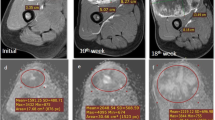

Illustrative example of IVIM parametric maps and corresponding histograms in tumor volume of representative patients with tumor involving different anatomical regions like femur, tibia and humerus are presented in Figs. 2, 3 and 4 respectively. No significant qualitative or quantitative reginal differences was observed in the IVIM parametric maps evaluated in different anatomical regions.”

18 years old male patient from good-response group, with localized osteosarcoma of 284 cc volume in right distal femur at baseline. Patient had > 90% histological necrosis after surgery and event free survival and overall survival of 54 months. 1st, 2nd and 3rd columns show images at time points t0 (baseline), t1 (after 1st cycle of chemotherapy) and t2 (after completion of chemotherapy) respectively and 4th column represents histograms of parametric maps in tumor volume at three time-points t0 (green), t1 (orange) and t2 (blue). a, b T2-weighted fat saturated image, c–e DWI (b = 800 s/mm2), f–h Apparent diffusion coefficient (ADC), i Histogram of ADC was high peaked and sharp at t0, moved towards the right of the coordinate and became wider at t1 and t2. j–l Diffusion coefficient (D), m Histogram of D was high peaked and sharp at t0, moved towards the right of the coordinate at t1 and t2. n–p Perfusion coefficient (D*), q Histogram of D* was highly peaked and positively skewed with a heavy tail at t0, became more positively skewed with a lighter tail at t1 and t2. r–t Perfusion fraction (f), u Histogram of f was highly peaked at t0 and became more positively skewed and wider at t1 and t2. v–x D*.f, y Histogram of D*.f was high peaked at t0 and became more positively skewed and high peaked at t1 and t2

12 years old male patient from poor-response group, with osteosarcoma of 554 cc volume in left tibia and multiple metastatic lung nodules at baseline. Patient had 35% histological necrosis in resected tumor specimen and event free survival and overall survival of 16.3 months. 1st, 2nd and 3rd columns show images at time points t0 (baseline), t1 (after 1st cycle of chemotherapy) and t2 (after completion of chemotherapy) respectively and 4th column represents histograms of parametric maps in tumor volume at three time-points t0 (green), t1 (orange) and t2 (blue). a, b T2-weighted fat saturated image, c–e DWI (b = 800 s/mm2), f–h Apparent diffusion coefficient (ADC), i Histogram of ADC was high peaked and sharp at t0 and slightly shifted to the right of the coordinate and became sharply peaked at t1 and t2. j–l Diffusion coefficient (D), m Histogram of D was high peaked and sharp at t0 and slightly shifted to the right of the coordinate and became sharply peaked at t1 and t2. n–p Perfusion coefficient (D*), q Histogram of D* was positively skewed with a heavy tail at t0, became highly peaked at t1 and turned to a wider & flat (low peaked) shape at t2. r–t Perfusion fraction (f), u Histogram of f was wide and low peaked at t0, became slightly positively skewed and high peaked at t1 and t2. v–x D*.f, y Histogram of D*.f was low peaked with long tail at t0 and became high peaked at t1 and more positively skewed at t2